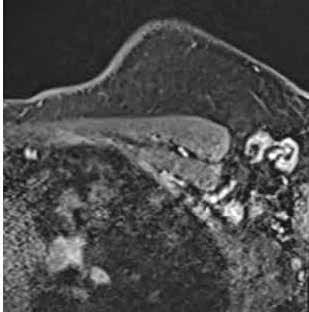

Ante la persistencia de la bradipsiquia y la dificultad para ejecutar órde nes moderadamente complejas, a pesar de que la madre decía que no veía grandes diferencias con respecto a su estado basal, se solicitó una resonan cia magnética cerebral. En la resonancia magnética se observó una altera ción de la intensidad de la señal en la porción central del cuerpo calloso, en concreto en esplenio y rodilla, con hiperintensidad en T2, hipointensidad en T1 basal y moderada restricción de la difusión; hallazgos que eran com patibles con el Síndrome Marchiafava-Bignami (Figura 3).

Figura 3.

Resonancia magnética. Secuencia T1 y T2. Cortes sagital y transversal. Estudio artefactado por el movimiento del paciente. Estudio T1 donde se aprecia una lesión hipointensa con moderada restricción a la difusión en las capas medias del esplenio del cuerpo calloso, que en la secuencia T2 corresponde con una lesión hipertensa. Esta lesión en dicha localización y en el contexto clínico del paciente es altamente sugestiva de Marchiafava-Bignami.